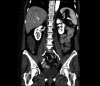

Incidentally discovered low-grade appendiceal mucinous neoplasm: a precursor to pseudomyxoma peritonei

Appendiceal mucoceles (AMs) infrequently arise from an underlying malignancy. Treatment has progressed toward a less aggressive approach over time; they can be managed by appendectomy-only unless pathology reveals malignancy. The ultimate goal of management is to prevent AM rupture, avoiding the syndrome of pseudomyxoma peritonei.